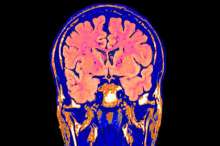

Американская биотехнологическая компания Bioquark планирует доказать, что смерть мозга не является необратимой, и разработать технологии «оживления» главного органа человеческого организма. Об этом сообщает The Daily Mail.

Пастор и ее коллеги запустили проект ReAnima — чтобы исследовать потенциал последних биомедицинских технологий для «реанимации» головного мозга. Ученые начнут клинические испытания с участием людей, которых в США и Великобритании официально признали мертвыми, но продолжают поддерживать в вегетативном состоянии («живые трупы»).

Уже получено разрешение на первый этап клинических испытаний. Исследователи будут работать с группой пациентов 15-65 лет, попавших в состояние мозговой смерти из-за черепно-мозговой травмы. С помощью пептидов, стволовых клеток, лазеров и стимуляции нервов ученые постараются добиться оживления тканей мозга.

Первые результаты ожидаются уже через два-три месяца. Исследователи надеются пронаблюдать (на томографе) симптомы оживления на границе верхнего отдела спинного мозга и нижней зоны мозгового ствола (этот участок, в частности, отвечает за дыхание и сердцебиение).